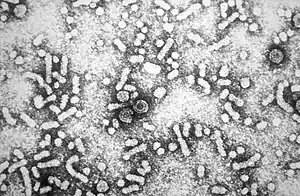

Viral infection

Viral infection with either hepatitis C virus (HCV) or Hepatitis B virus (HBV) is the chief cause of liver cancer in the world today, accounting for 80% of hepatocellular carcinoma (HCC).[13][14][15] The viruses cause HCC because massive inflammation, fibrosis, and eventual cirrhosis occurs within the liver. HCC usually arises after cirrhosis, with an annual incidence of 1.7% in cirrhotic HCV-infected individuals.[16] Around 5-10% of individuals that become infected with HBV become chronic carriers, and around 30% of these acquire chronic liver disease, which can lead to HCC.[13] HBV infection is also linked to cholangiocarcinoma.[17] The role of viruses other than HCV or HBV in liver cancer is much less clear, even though there is some evidence that co-infection of HBV and hepatitis D virus may increase the risk for HCC.[18]

Many genetic and epigenetic changes are formed in liver cells during HCV and HBV infection, which is a major factor in the production of the liver tumors. The viruses induce malignant changes in cells by altering gene methylation, affecting gene expression, and promoting or repressing cellular signal transduction pathways. By doing this, the viruses can prevent cells from undergoing a programmed form of cell death (apoptosis) and promote viral replication and persistence.[13][16]

HBV and HCV also induce malignant changes by causing DNA damage and genomic instability. This is by creating reactive oxygen species, express proteins that interfere with DNA repair enzymes, and HCV causes activation of a mutator enzyme.[19][20]